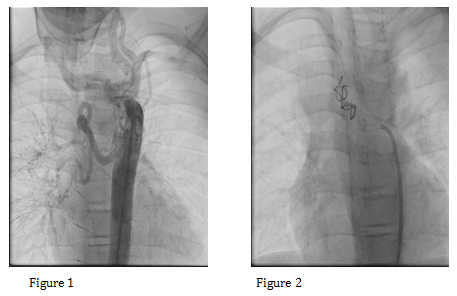

A total of 45 patients with TOF with pulmonary stenosis underwent MAPCAs coiling during Jan 2011 to Dec 2014. These patients had previous cardiac catheterization and planned for transcatheter MAPCAs coiling one day before or on the day of surgery. All patient who had significant MAPCAs (>2mm) were included in the study. The patients were admitted in the hospital and a written consent was taken before the procedure. A complete blood picture, c-reactive protein, renal functions and saturations were taken before the procedure. We continuously monitor the saturations throughout the procedure and after the MAPCAs coiling till the patient undergoes for total correction. After femoral arterial access, an aortogram was done with pigtail in all the patients to visualize the MAPCAs. Then the MAPCAs were engaged with Judkin Right (JR) catheter and selective angiogram was done for origin, size and distribution of MAPCAs. The JR catheter advanced as far as possible from the main vessel into the collateral and free coil taken and load into the catheter and advanced with the hard end of .038 guide wire. The cook free coils delivered in the collaterals and then contrast injection given to check for any residual leak or other collateral (Figure 1&2). After completion of the procedure the patients were shifted to ward for monitoring and then preparation for total correction.

The closure can be done by two ways either surgical ligation or transcatheter embolization.22,23 The surgical ligation requires extensive surgery and tissue damage, difficult to locate, excessive blood loss and prolongs the procedure time. However large MAPCAs may be easily located by the expert surgeon and ligated. In the recent years the emerging technique of percutaneous approach is easy and effective as in our study all patients (n=45) had successful closure (Figure 1 & 2). The mean procedure time remained 55min. sometimes one may have difficulty via transcatheter coiling as in one of our patient MAPCAs were arising from left subclavian artery and had difficulty in engaging the collaterals so the procedure time was prolonged, however MAPCAs from descending aorta were straight forward with much less procedure and fluoroscopic time.

Figure 1&2 Showing large MAPCA and in situ cook free coils resulting complete occlusion.